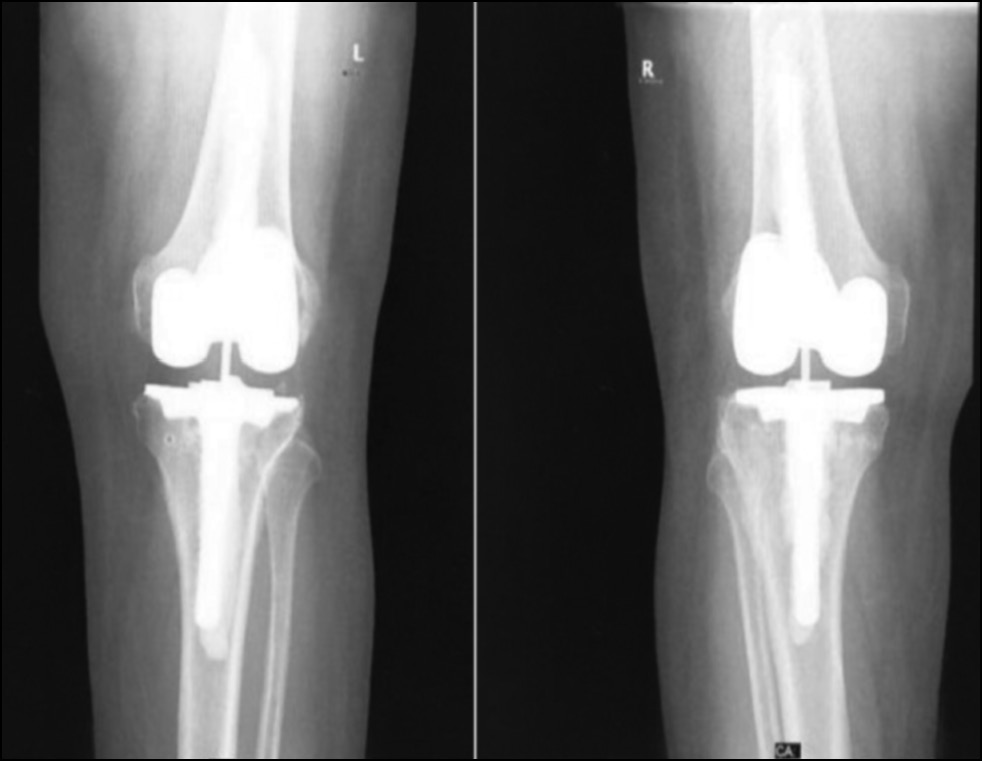

Radiological assessment (Fig. 11–14)

Fig. 13. Ap postoperative x-ray showing bilateral total knee arthroplasty.

Рис. 13. Послеоперационная рентгенограмма с двусторонней тотальной артропластикой коленного сустава.